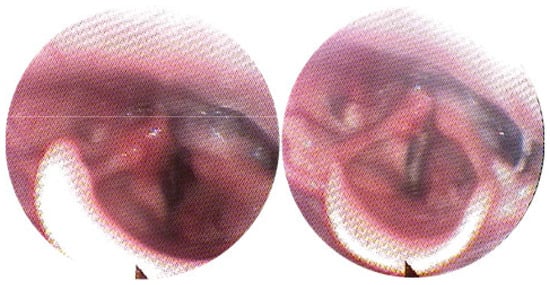

3.1. Magnetic Resonance Imaging (MRI) Findings

3.2. Clinical Outcomes

- Complete response: 100% reduction in lesion volume.

- Significant reduction: volume reduction of more than 50% but less than 100%.

- Limited reduction: volume reduction of less than 50%.